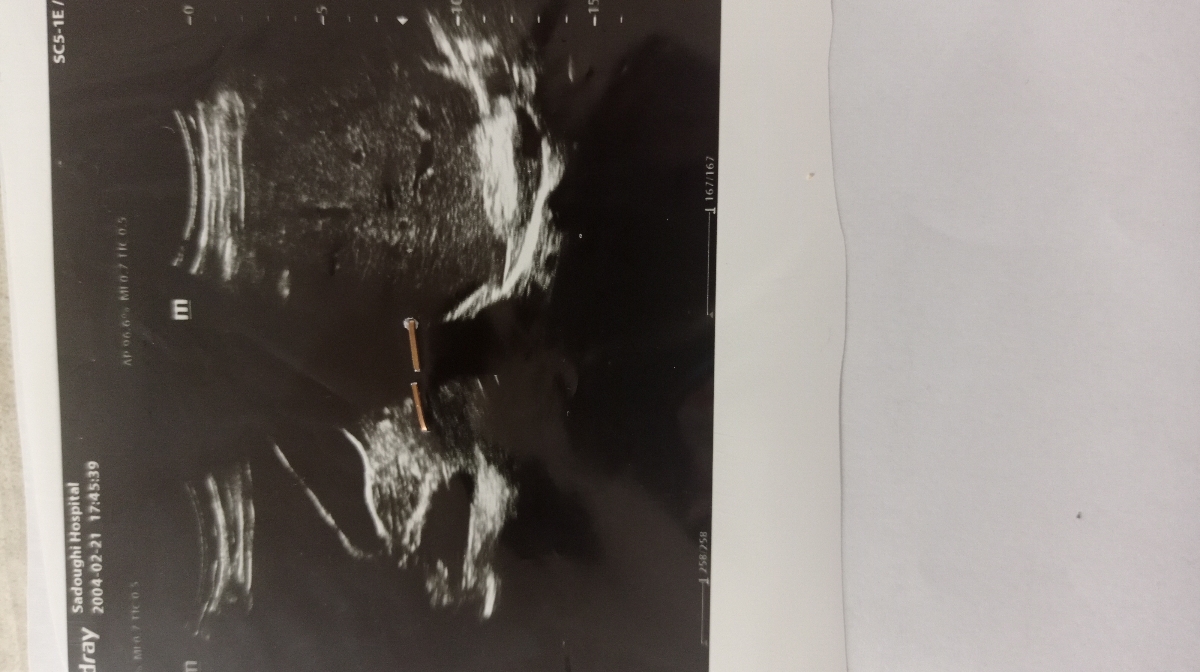

دکتر جواب این سنو چی میشه

کبد چرب گرید ۱ دارید

مشکل‌ ندارد فقط کبد چرب خفیف تایید شده سطح آنزیم های کبدی چک گردد